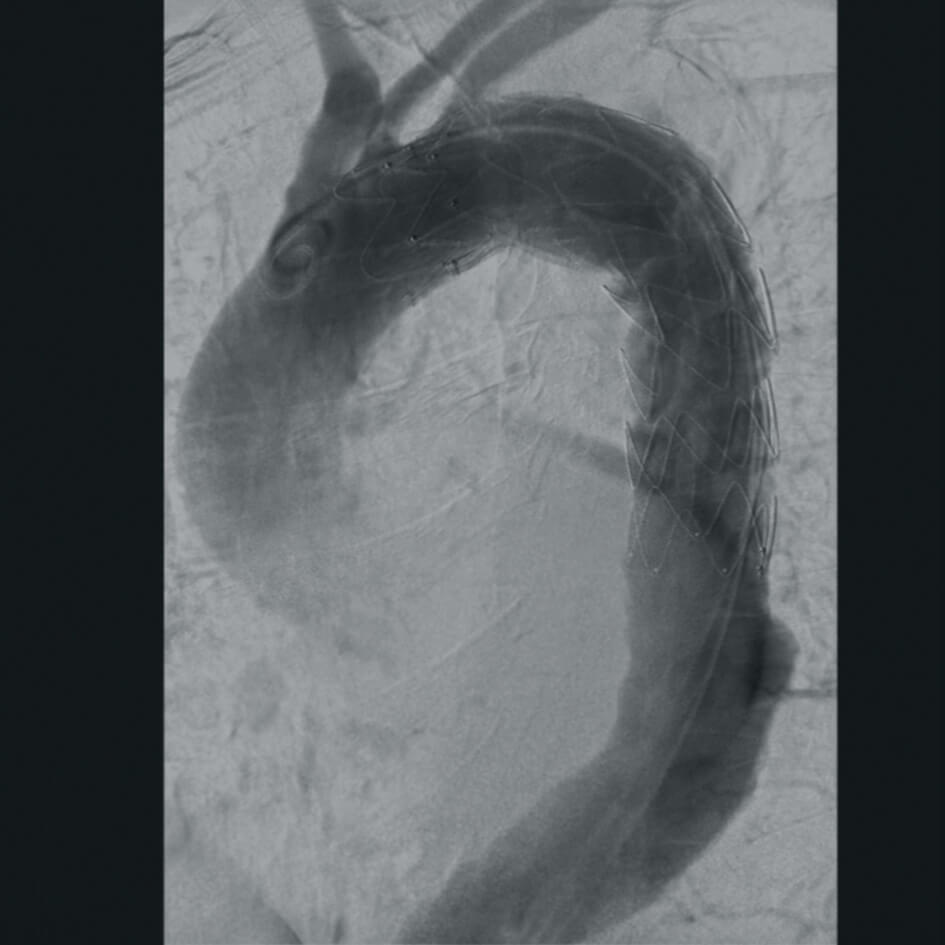

Полное отсутствие искажений снимков в сочетании с высоким динамическим диапазоном широко востребованы как при сложных операциях в нейрохирургии, сосудистой хирургии, инвазивной радиологии, так и в гибридных областях применения, а также в ортопедии, травматологии. В сосудистой хирургии особенно важны высокий динамический диапазон и пространственное разрешение, обеспечивающие детальную визуализацию даже мельчайших сосудов. Специализированное программное обеспечение SmartVascular позволяет проводить настройку системы для васкулярных операций и сосудистой хирургии.

Впервые в мировой практике в Vision RFD 3D используется невероятно компактный моноблочный генератор для импульсной рентгеноскопии с увеличенной резервной мощностью и вращающимся анодом рентгеновской трубки для улучшения качества изображений при минимальной интенсивности облучения. Продолжительность импульсов можно регулировать в диапазоне от 7 до 40 мс, что существенно повышает четкость снимков. Vision RFD 3D отлично подходит для использования в клинических процедурах типа: чрескожная транслюминальная коронарная ангиопластика или коронарная ангиография.